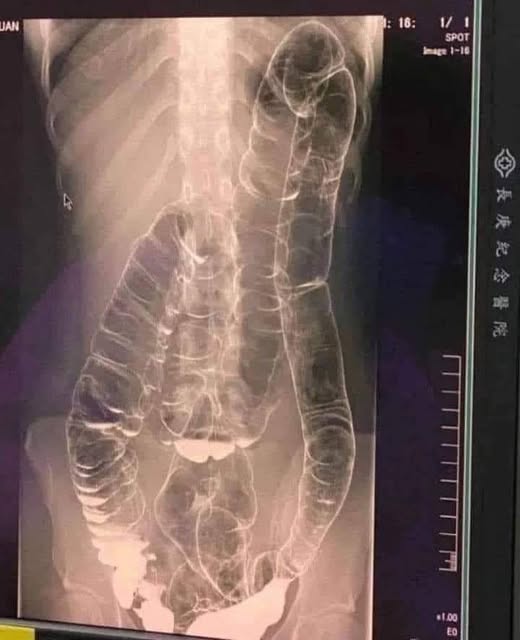

Wer hat nicht schon einmal unter Verstopfung gelitten? Dieses Problem wird oft als trivial angesehen, kann aber zu einem Albtraum werden, wenn es chronisch wird. Stellen Sie sich vor, Sie haben seit mehr als zwei Wochen keinen Stuhlgang mehr gehabt. Genau das passierte einer jungen Frau, deren Dickdarm überlastet war und die sich gefährlich erweiterte. Ein Extremfall, aber ein klares Beispiel für die ungeahnten Gefahren einer langfristigen Verstopfung. Wie können wir verhindern, dass diese Verdauungsstörung ernst wird?

Wenn du keinen regelmäßigen Stuhlgang hast, sammelt sich der Abfall im Dickdarm an. Das Ergebnis: übermäßiger Druck, der Schmerzen, Blähungen und in den schwersten Fällen schwerwiegende Komplikationen verursachen kann .

- Erweiterung des Dickdarms : Mit der Zeit verliert der Dickdarm an Elastizität und es wird immer schwieriger, den Stuhl zu entfernen.